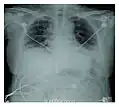

Radiographie montrant une réduction marquée de la capacité pulmonaire_Idiopathic_DAD_3.jpg)